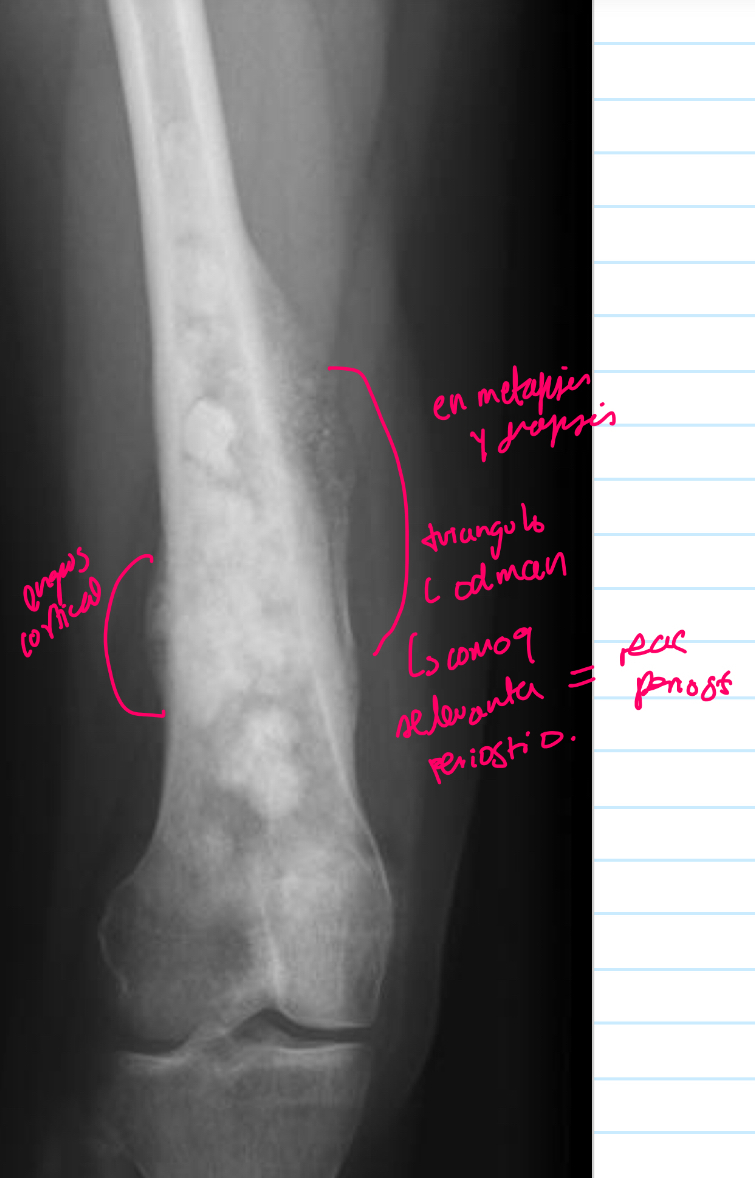

11

Q

q se ve q tiene

A

Engrosamiento de la cortical

Reac periostica: como q se levanta el periostico

Triangulo de codman

14

Otro ejemplos de osteosarcoma